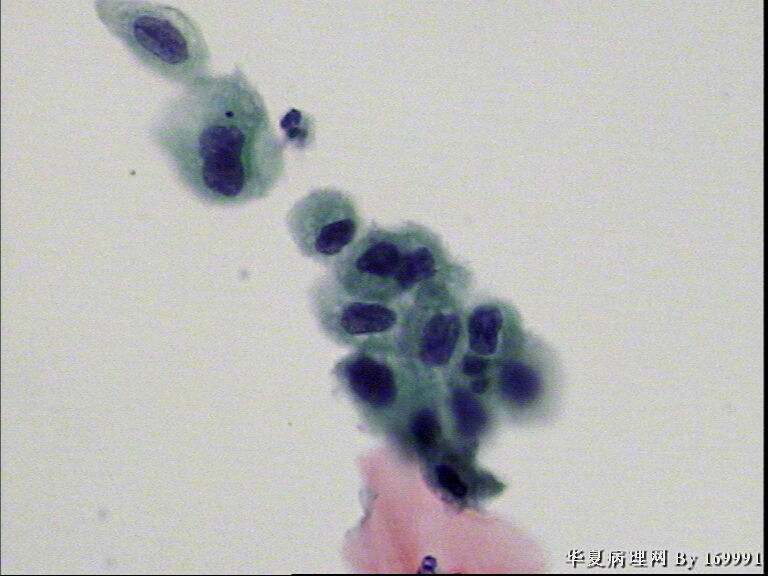

宫颈液基,患者,23岁,宫颈中糜

• 宫颈液基,患者,23岁,宫颈中糜图4

图4

我感觉报HSIL有点高了,就细胞的形态来看,核增大深染的基本上还是中层以及接近表层的细胞,结合患者年龄,我认为报LSIL更好一些。不知道对不对,请各位老师指教啦!

大家都看得不错。最高可能是CINII级,看活检了。

感觉像高级别,但患者年龄太小。ASC-H